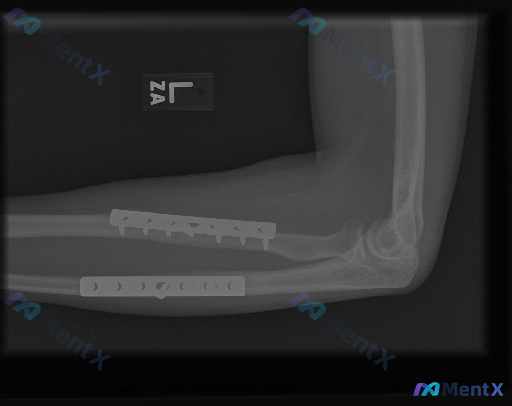

左前臂双骨折术后X光:报告写“修复良好”,但提示存在异常,问题在哪?

整理了一份左前臂尺桡骨近端双骨折术后的侧位X光资料,有点意思——

- 尺桡骨近端都有钢板螺钉内固定,位置看起来不错,螺钉都穿透皮质了,没看到明确松动、断裂

- 钢板覆盖区没见明显透亮骨折线,还有骨痂生长,骨折线模糊

- 肘关节对应关系、关节间隙、骨质密度、软组织也都没报明显异常

但这份资料同时明确标注了“存在异常”。

如果不只是“术后正常改变”,大家第一眼会优先往哪个方向想?有没有什么容易在侧位片上被漏掉的细节?